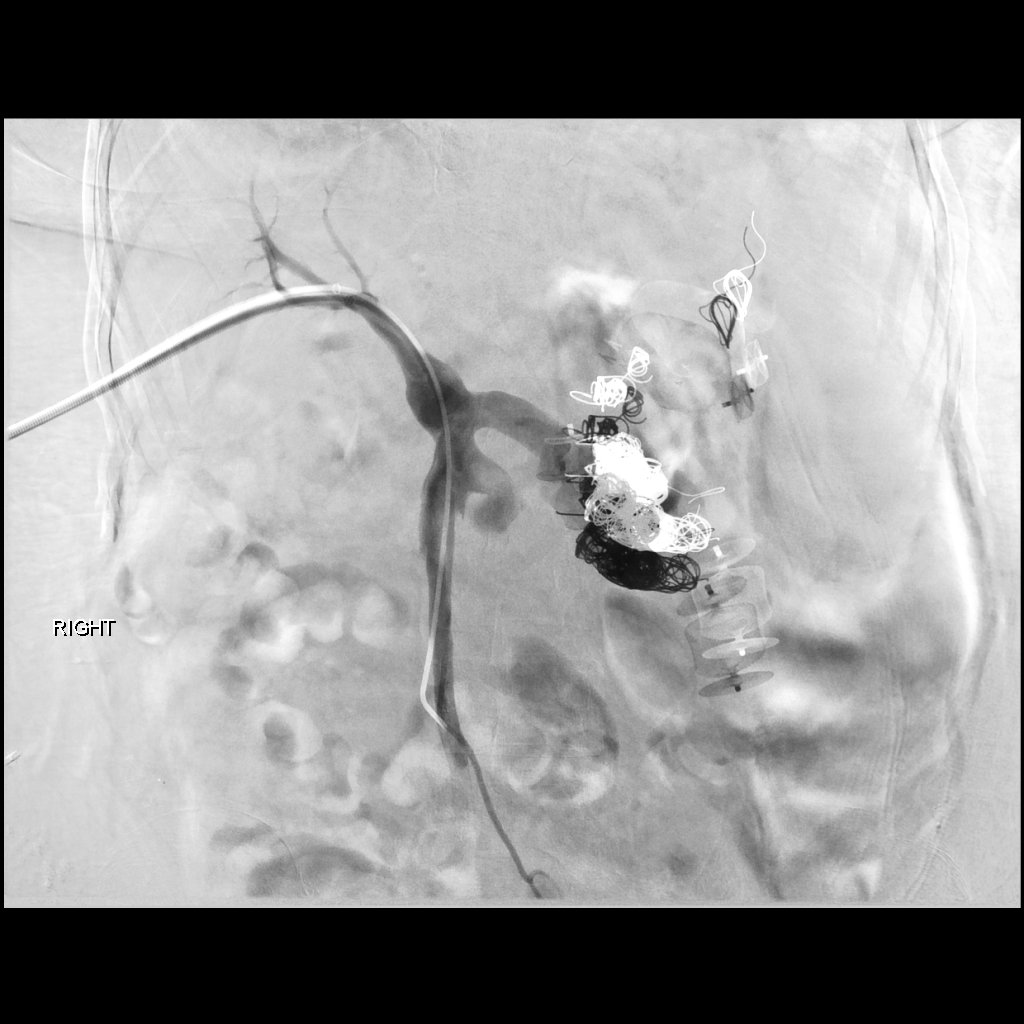

porto-systemic shunt- trans-hepatic access- 2 hrs,43 coils,2 plugs- @SIRRFS #irad #foamir #kitchensink #emptyshelves